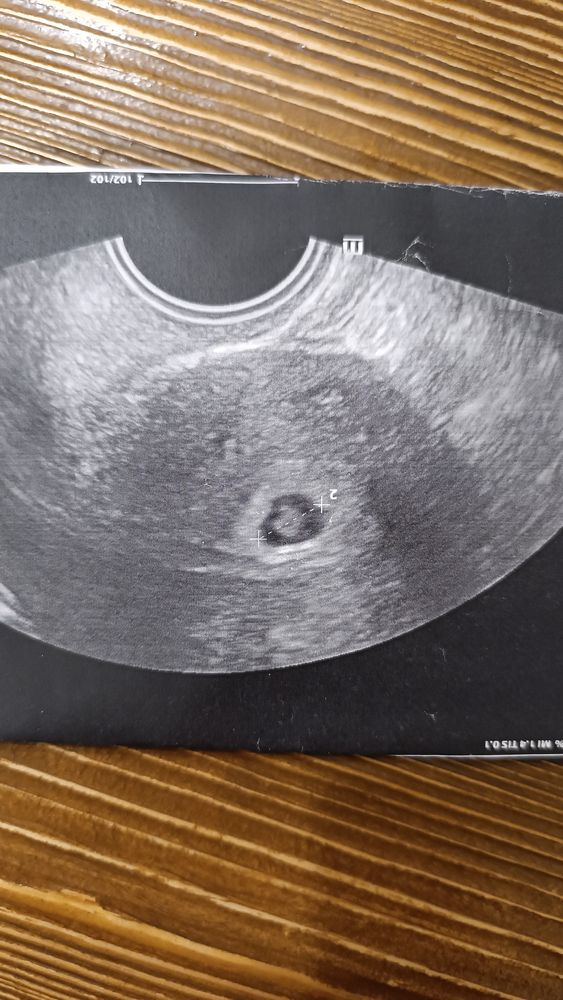

УЗИ 23 дпп фото

Ох не знаю мне вот видно эмбриончик!!🙏🏻 пускай растет малыш и уже след узи с сб 🙏🏻

Make a Dream, Спасибо, да очень жду))) Врач тоже увидела но ждет что бы наверняка)

Лиза, анембрионии нет по УЗИ это видно.По поводу хгч миллион хороших исходов

Лиза, обычно при а/б и желточного мешочка нет. не будьте такой злой